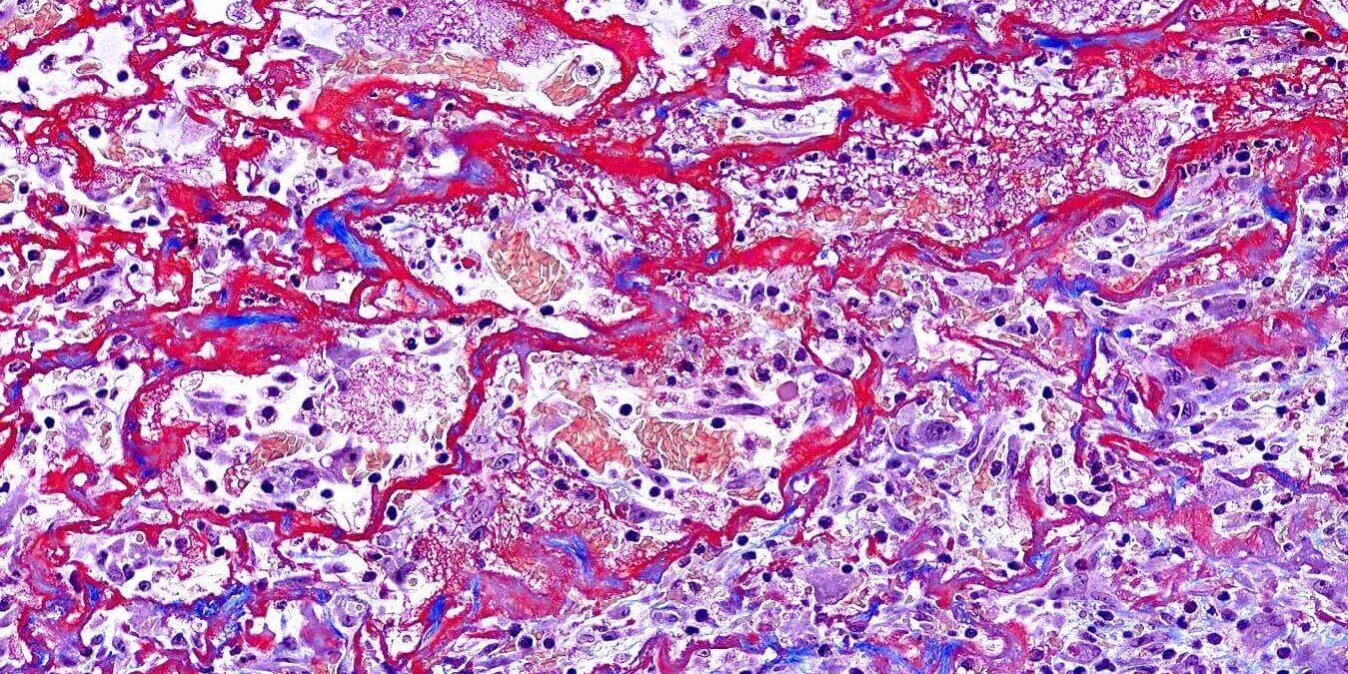

12 月232021立眾病理 皮膚傷口的Masson Trichrome染色 大量紅染的纖維素(fibrin)、膠原纖維(collagen fiber)、滲出液(exudate),還有新生的肉芽組織(granulation tissue)整個混雜在一起,看起來很藝術 —————— 👍👍👍Masson Trichrome染色試劑套組:TASS01 —————— Post navigationPreviousPrevious post:狗的睪丸腫瘤 – 精細胞瘤 seminomaNextNext post:藻類 – 狗貓意想不到的致命殺手!Related PostsModified Movat’s Pentachrome 染色法2022-07-22可見光免疫組織化學染色雙染 Immunohistochemical double staining2022-02-22Safranin O stain 番紅染色2022-02-22最佳的免疫化學染色IHC試劑套組2022-02-22可見光免疫組織化學染色雙染 Immunohistochemical double staining2022-02-22帶大家快速的認識各種切片染色技術!!2022-02-21